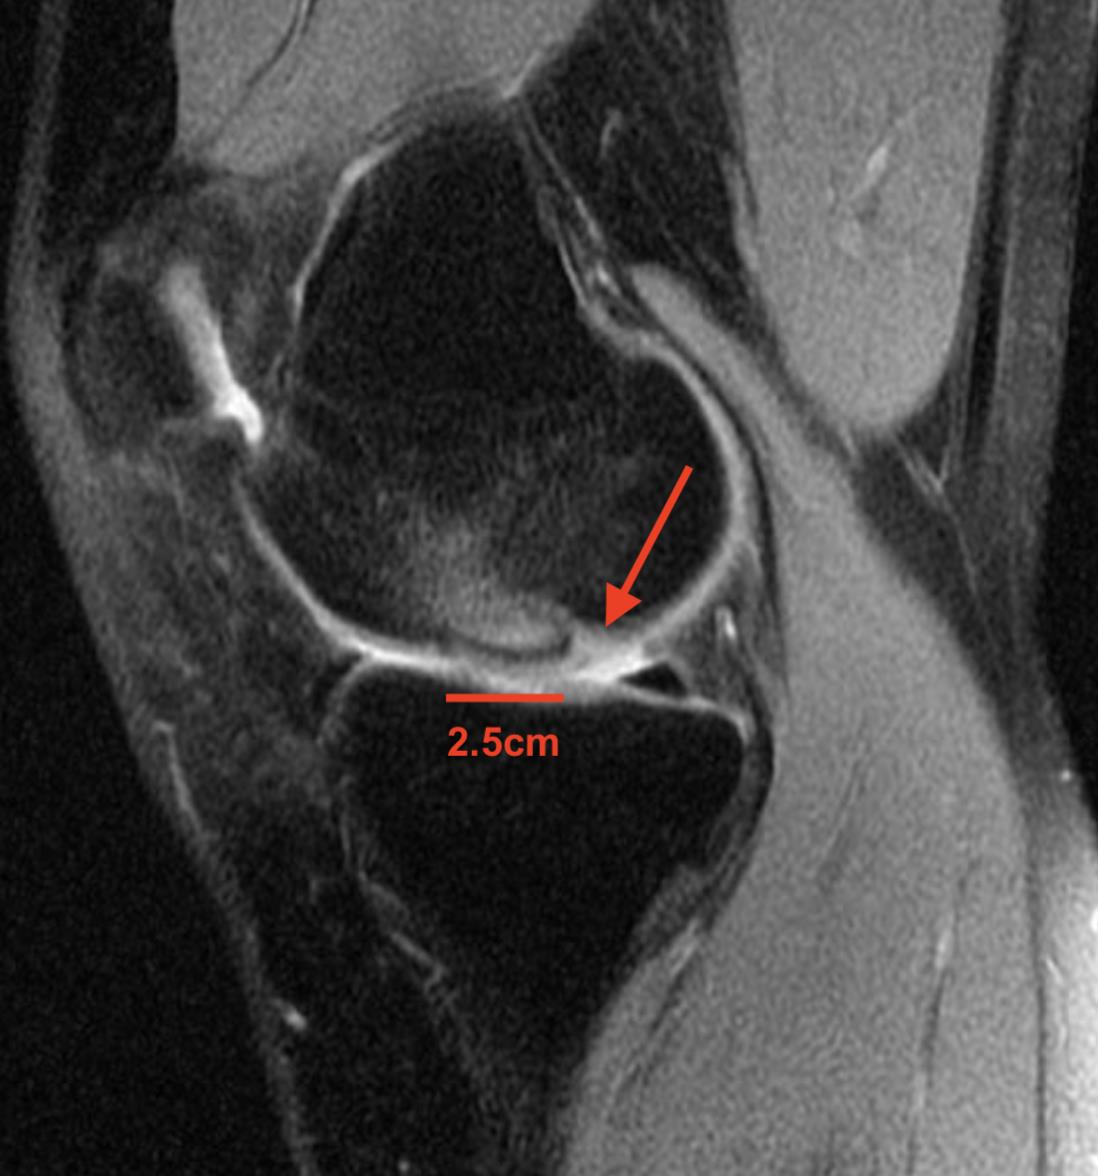

The patient has evidence of an unstable osteochondritis dissecans (OCD) lesion of the lateral aspect of the medial femoral condyle. Given that he is skeletally mature with an unstable lesion, an attempt at internal fixation is recommended.

Osteochondritis Dissecans (OCD) represents a pathologic lesion affecting juvenile patients' articular cartilage and subchondral bone, most typically of the posterolateral aspect of the medial femoral condyle. Diagnosis may be made radiographically but can be missed, with an MRI usually required to determine the size and stability of the lesion and to document the degree of cartilage injury. Treatment varies based on skeletal maturity and severity of the lesion. Definitive treatment can be non-operative with bracing and restricted weight bearing in children with open physes. But surgical treatment is preferred in older patients with closed physes and for lesions that are unstable. Unstable lesions are those with circumferential fluid signal (Illustration A) that indicates displacement of the cartilage from the subchondral bone; however, arthroscopic findings of a break in the articular cartilage or a mobile flap detected using the arthroscopic probe are the gold standard in diagnosis.

Figures A and B are AP and lateral radiographs demonstrating incongruence of the lateral aspect of the medial femoral condyle consistent with an OCD lesion in a skeletally immature individual. Figures C and D represent coronal and sagittal fluid-sensitive MRI sequences showing a ~ 2.5 x 2 cm OCD lesion of the medial femoral condyle with fluid circumferentially surrounding the cartilage fragment indicating an unstable lesion. Illustration A denotes the area of the cartilage flap that allows for the subchondral fluid to accumulate.